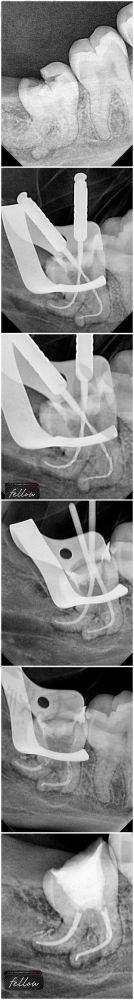

治疗中包含了现如今主流技术——机械根管扩展+热牙胶充填,提升密封精度的同时,也显著降低术后并发症的概率。相比传统方式,中喜口腔采用的流程时间更短,疼痛感也显著减轻,非常适合对疼痛较为敏感的人群。

同时,医生在整个根管治疗过程中会通过显微镜或者高清口腔镜头展示治疗细节,让患者看得明白、治疗得安心。术后则会有专精护理人员提供定期回访服务,记录修复情况,防止治疗后复发。

特别多初次接触这个手术名词的朋友,可能会困惑:根管治疗到底是干什么的?通俗地讲,它相当于“牙齿里的清根修复术”。我们的牙齿里面藏着一堆微细的“纳米毛细根管”,当龋齿感染深入牙髓后,细菌就会沿着这些根管扩散,造成剧痛甚至牙齿失活。

而根管治疗,就是清理这些受感染或坏死的牙髓组织,然后进行消毒、填充,再通过牙冠封闭,维持牙齿功能的保留性治疗。特别多人说它是“保牙利器”,绝非夸张!其实每年在国内完成的同类型治疗项目上百万例,已经成为牙医日常工作中使用更频繁的项目之一。

院内使用的均为国内外认证设备,包括德国KaVo牙椅系统、德国VDW根管马达、高清CBCT影像技术等,全程实现电子化诊疗,并配备专属口腔数据档案系统,让就医信息更系统、更科学。

坐诊医生李文强医师拥有10年以上口腔临床工作经验,擅长根尖周炎、急性牙髓炎等疑难根管治疗。他倡导“细根不放过,病根一扫光”的理念,认为光设备精良远远不够,医生手法细致与病灶图谱的分析配套,是决定治疗成败的关键。